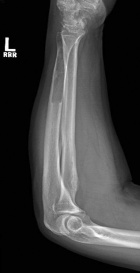

62 year old male began having trouble with his left wrist and forearm after shoveling snow 5 months prior to evaluation. Pain is improving.

Zoom image: Radiological image Radiological image.